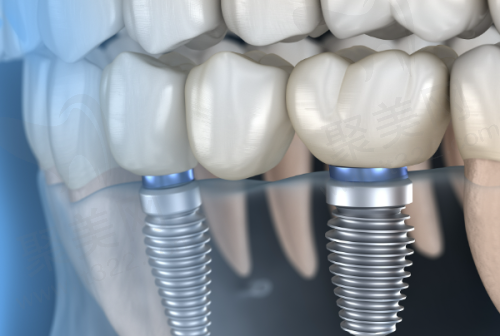

即拔即种植牙技术的较大优势在于能够大大缩短治疗时间。传统的种植牙修复通常需要分多个阶段进行,而即拔即种则允许患者在拔牙后立即进行种植,减少了多次就诊的麻烦和痛苦。这种方法特别适合那些希望尽快修复口腔功能的患者,尤其是年轻人和工作忙碌的上班族。

此外,即刻种植还能有效减少牙槽骨的吸收。在拔牙后,牙槽骨会面临一定程度的吸收,而即刻种植则通过立即植入种植体帮助保持牙槽骨的形态和高度,这对后期的种植成效至关重要。

然而,即拔即种植牙并非没有缺陷。其较大的劣势在于对医生的技术水平要求较高。因为即刻种植需要在拔牙后立即进行植体植入,若此时创面存在炎症或医生技术不过关,便可能导致种植失败,患者面临再次手术的风险。

此外,并不是所有患者都适合这种方法。那些牙槽骨条件比较差、骨量不足的患者就不适合进行即拔即种。即使进行种植,骨结合的成效也可能不理想,导致种植体的松动和失败。